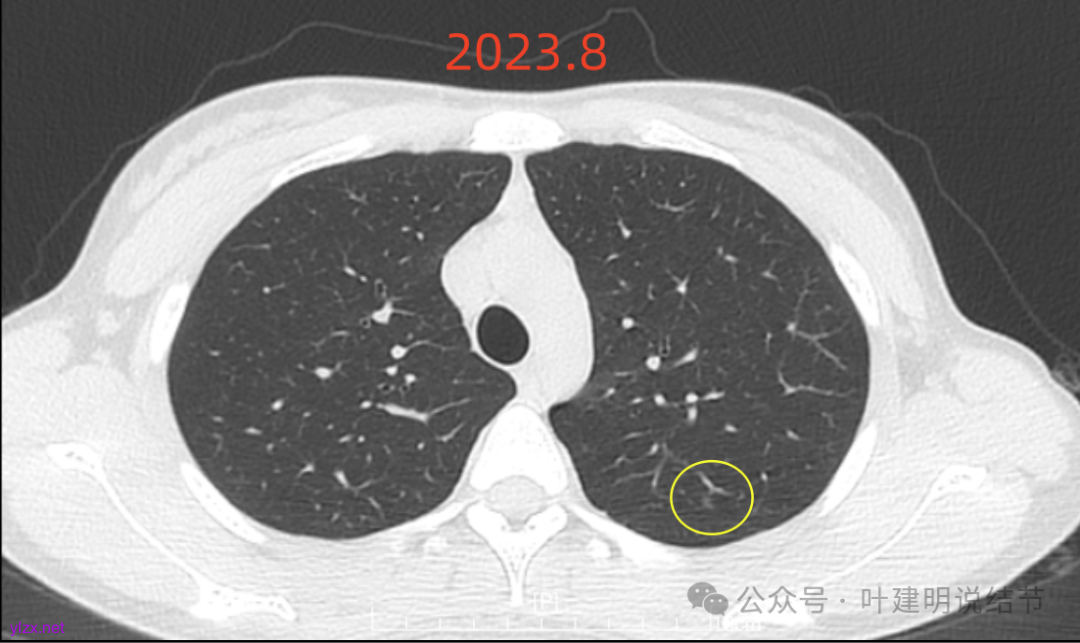

先来看2023年8月的:

病灶6:右下叶脊柱旁囊腔型病灶,整体轮廓与边界清,没有明显实性成分,考虑原位癌或微浸润性腺癌可能性大。